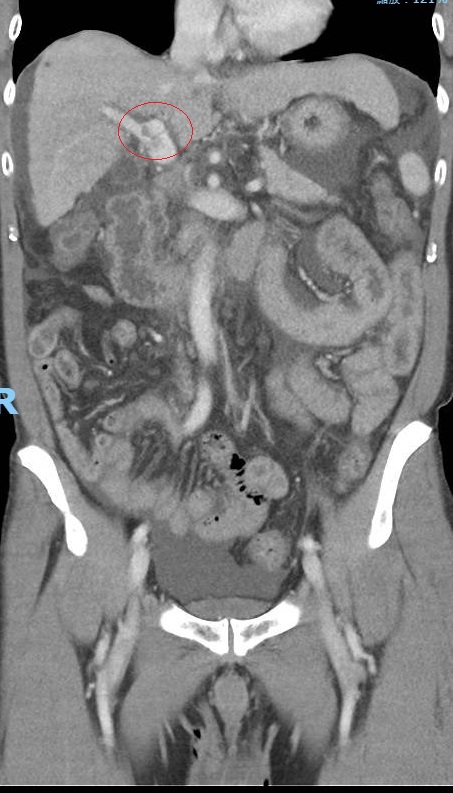

53歲詹姓男子擴散到肝門靜脈的腫瘤。(記者葉靜美翻攝)

詹男肝門靜脈的腫瘤幾乎消失。(記者葉靜美翻攝)